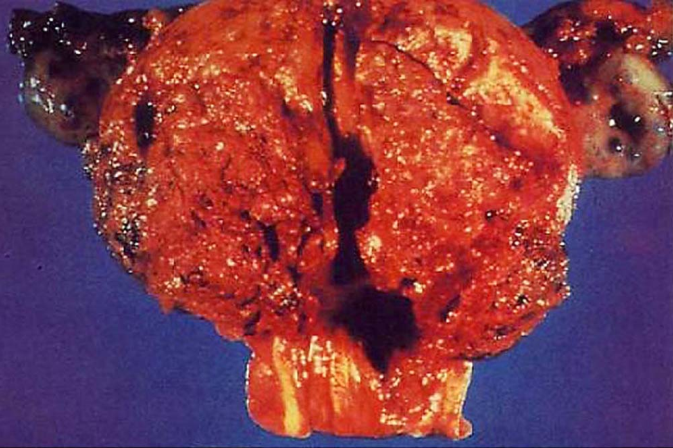

绒癌的大体观见肿瘤位于子宫肌层内,可突向宫腔或穿破浆膜,单个或多个,大小不等,无固定形态,与周围组织分界清,质地软而腌,海编样,暗红色,伴明显出血坏死。镜下见肿瘤细胞由细胞滋养细胞、合体滋养细胞及中间型滋养细胞组成,成片状高度增生,明显异型,不形成绒毛或水泡状结构,并广泛侵入子宫肌层造成出血坏死。肿瘤不含间质和自身血管,瘤细胞靠侵蚀母体血管而获取营养。

绒癌大体观 绒癌镜下观(200×)

肿瘤由细胞滋养细胞及合体滋养细胞组成, 看不到绒毛,伴出血坏死